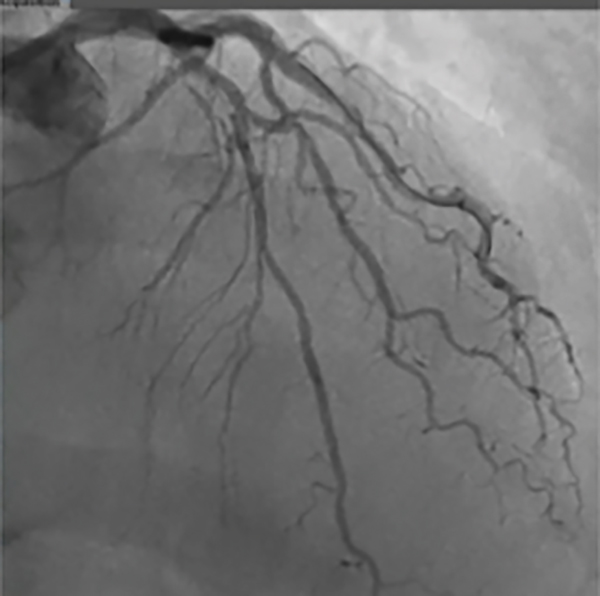

Figure 2

• The physician recognized the severity of the disease and the challenges of delivering interventional devices

• The decision was made prior to the case to utilize the GUIDEZILLA™ II Guide Extension Catheter for support in delivering various devices

• Due to severe overlay, a selective angiogram utilizing the GUIDEZILLA II Guide Extension Catheter (Figure 2) was performed and demonstrated a > 70% lesion in both the LAD and ostium of D1